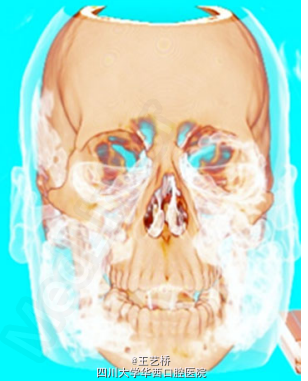

患者拔除双侧智齿后当天出现面部肿胀

检查发现患者整个面部肿胀,皮温正常,睁眼困难,轻度张口受限,轻度呼吸急促。触诊发现眶周、脸颊部、锁骨上窝有清脆捻发音。口内拔牙窝未愈合。

诊断:皮下气肿。患者住院进行预防性抗感染治疗,服用类固醇,同时为了避免软组织内气压过大,使用引流管控制气压

皮下气肿是颌面外科中较罕见的并发症,大多数情况下能够自行消退,但仍有少数情况会发生空气向面部深层组织扩散,严重者危机生命,因而皮下气肿的快速诊断极为重要,可以通过面部肿胀和捻发音判断。doi: 10.1093/jscr/rjv068